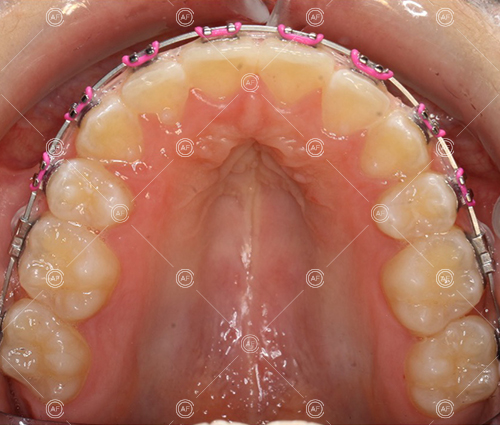

about this case…MH presented with class 1 incisors on the class 1 skeletal base with a slightly increased vertical proportion. She had severe crowding in the upper arch and moderate crowding in the lower. Due to the crowding in the lower arch, the lower centre line was off to the left by 2mm.

Buccal segments were essentially class 1 on the right hand side and a full unit class 2 on the left. This is due to buccal exclusion of the upper left 3 and mesial drift of the upper buccal segment.